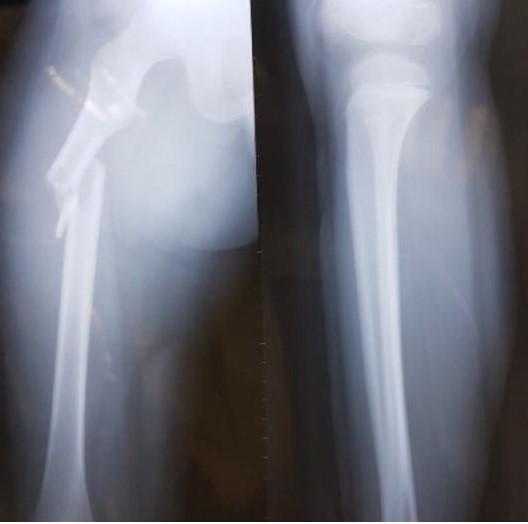

Cùng ngày, cháu được đưa đi cấp cứu tại Bệnh viện Nhi Trung ương. Theo bác sĩ, Kiên bị gãy xương đùi phải nhưng bó bột không thành công vì vết thương quá nặng. Nam sinh được chuyển sang Bệnh viện Việt Đức, Hà Nội. Bác sĩ chỉ định em phải mổ, nẹp vít xương.

Theo bác sĩ, nếu Kiên chỉ chạy chơi trong sân trường, em khó bị gãy xương đùi. Đây là bộ phận cứng, người không có bệnh lý về xương phải bị lực tác động mạnh mới có thể gây tổn thương. Đồng thời, Kiên có vết xước sau hông trái, dự đoán sau khi bị đâm mạnh, cháu ngã ngửa về phía sau.

Hình ảnh khi xương đùi của học sinh Trần Chí Kiên được chụp X-quang. Ảnh: NVCC.